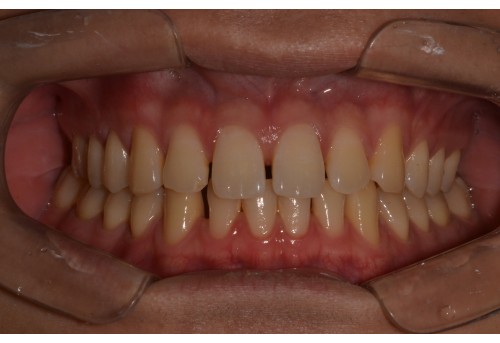

체리 증례집

• 전체

• 치아교정

• 임플란트

• 체리네이트